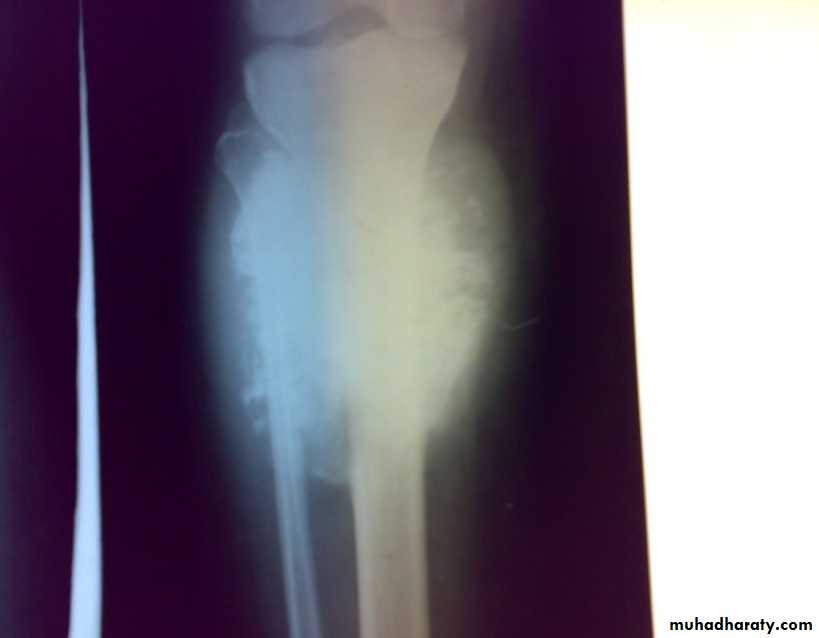

X-ray show eccentric osteolytic lesion in the end of long bone ,subchondral, trabeculated (soap bubble appearance). The cortex is thin, expanded or even perforated.

Patient presented by local pain and swelling or pathological fractures. Common site is the distal femur, proximal tibia, distal radius.